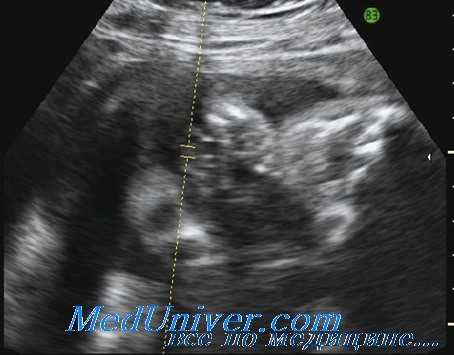

- Фетометрия плода. Ультразвуковое измерение окружностей головы, живота, грудной клетки, бипариетального и лобно-затылочного размеров, длины трубчатых костей предоставляет объективные данные о развитии плода. Полученные показатели сравнивают с нормативными для каждого периода гестации.

2. Ультразвуковая биометрия

Окружность живота и предполагаемая масса плода - наиболее достоверные диагностические показатели для определения маловесного плода. Наиболее ценный показатель - это предполагаемая масса плода. Данный показатель базируется на измерении окружности головы, окружности живота и длины бедра. Ценность метода заключается в его динамическом наблюдении.